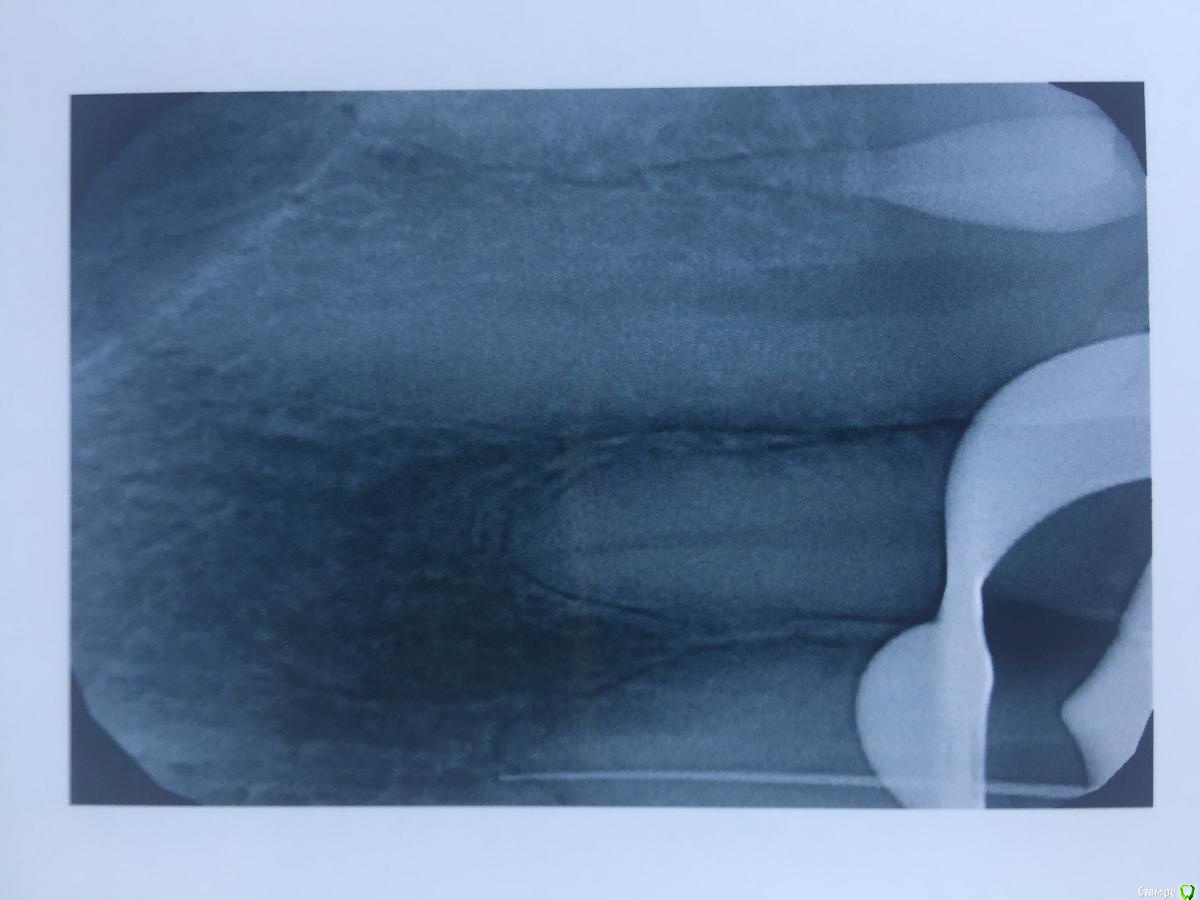

alina39 Опубликовано 9 декабря, 2016 Автор Поделиться Опубликовано 9 декабря, 2016 (изменено) Сделали новую КТ, подтвердился диагноз кистогранулема, почти киста по размерам.В прикрепленных - скриншот кт зуба.А главное боль не проходит, промыли и кальций положили неделю назад а боль не унимается, болит как рана и изредка дергает немного.Был один светлый период - 3 недели назад - когда зуб открыли, сказали полоскать и он неделю после этого не болел совсем, а потом все по новой. Изменено 9 декабря, 2016 пользователем alina39 Ссылка на комментарий

alina39 Опубликовано 9 декабря, 2016 Автор Поделиться Опубликовано 9 декабря, 2016 (изменено) покажите снимки на стадии леченияДругих снимков нет, сначала делали рентген, но на нем кисты не было видно, и потом вот два КТ: первый скриншот - это КТ 3 дня назад, а два других - 3 недели назад. Изменилось ли что-то за эти 3 недели? Изменено 9 декабря, 2016 пользователем alina39 Ссылка на комментарий